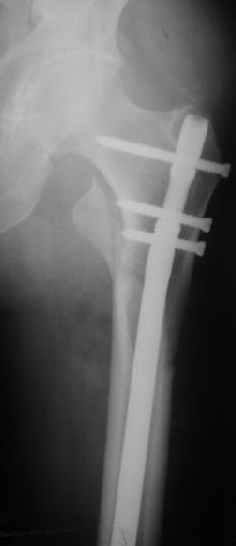

В частности, на проксимальном конце сделано еще одно дополнительное статическое отверстие. Можно ввести в проксимальном отделе 4 винта, из них 3 статические (2 в круглые отверстия и 1 по нижнему краю овального). Картинки в приложении. На дистальном конце стержня тоже кое-что улучшено. Спрашивайте в аптеках, как говорится. Выпускается предприятием "ЦИТО" (Москва), то есть это малобюджетное решение.

Конечно, мы не синтезируем остеопорозые вертельные переломы согласно прилагаемому примеру, винты 6 мм вырежутся. Но у более молодых при хорошем качестве кости такие или подобные гвозди с поперечным расположением винтов вполне применимы для меж- и подвертельных переломов.

Женя, эта картинка показывает не оптимальное лечение вертельных переломов в моем представлении, а особенности дизайна упомяутого фиксатора.

В частности, его возможности при фиксации переломов проксимального отдела бедра - в сравнении с другими, имеюшими лишь по одному статическому и динамическому отверстию и с кондуктором для введения 2 винтов.

Это было года 2,5 назад, мы тогда еще уточняли возможности шинирования с угловой стабильностью гвоздем с поперечным расположением винтов при переломах проксимального отдела бедра. Пациенту не пришлось приобретать намного более дорогой рекон или проксимальный гвоздь. В приложении еще несколько примеров применения того гвоздя при высоких переломах бедра, в том числе с более латеральной точкой входа. Гвоздь изгибаем для этого.